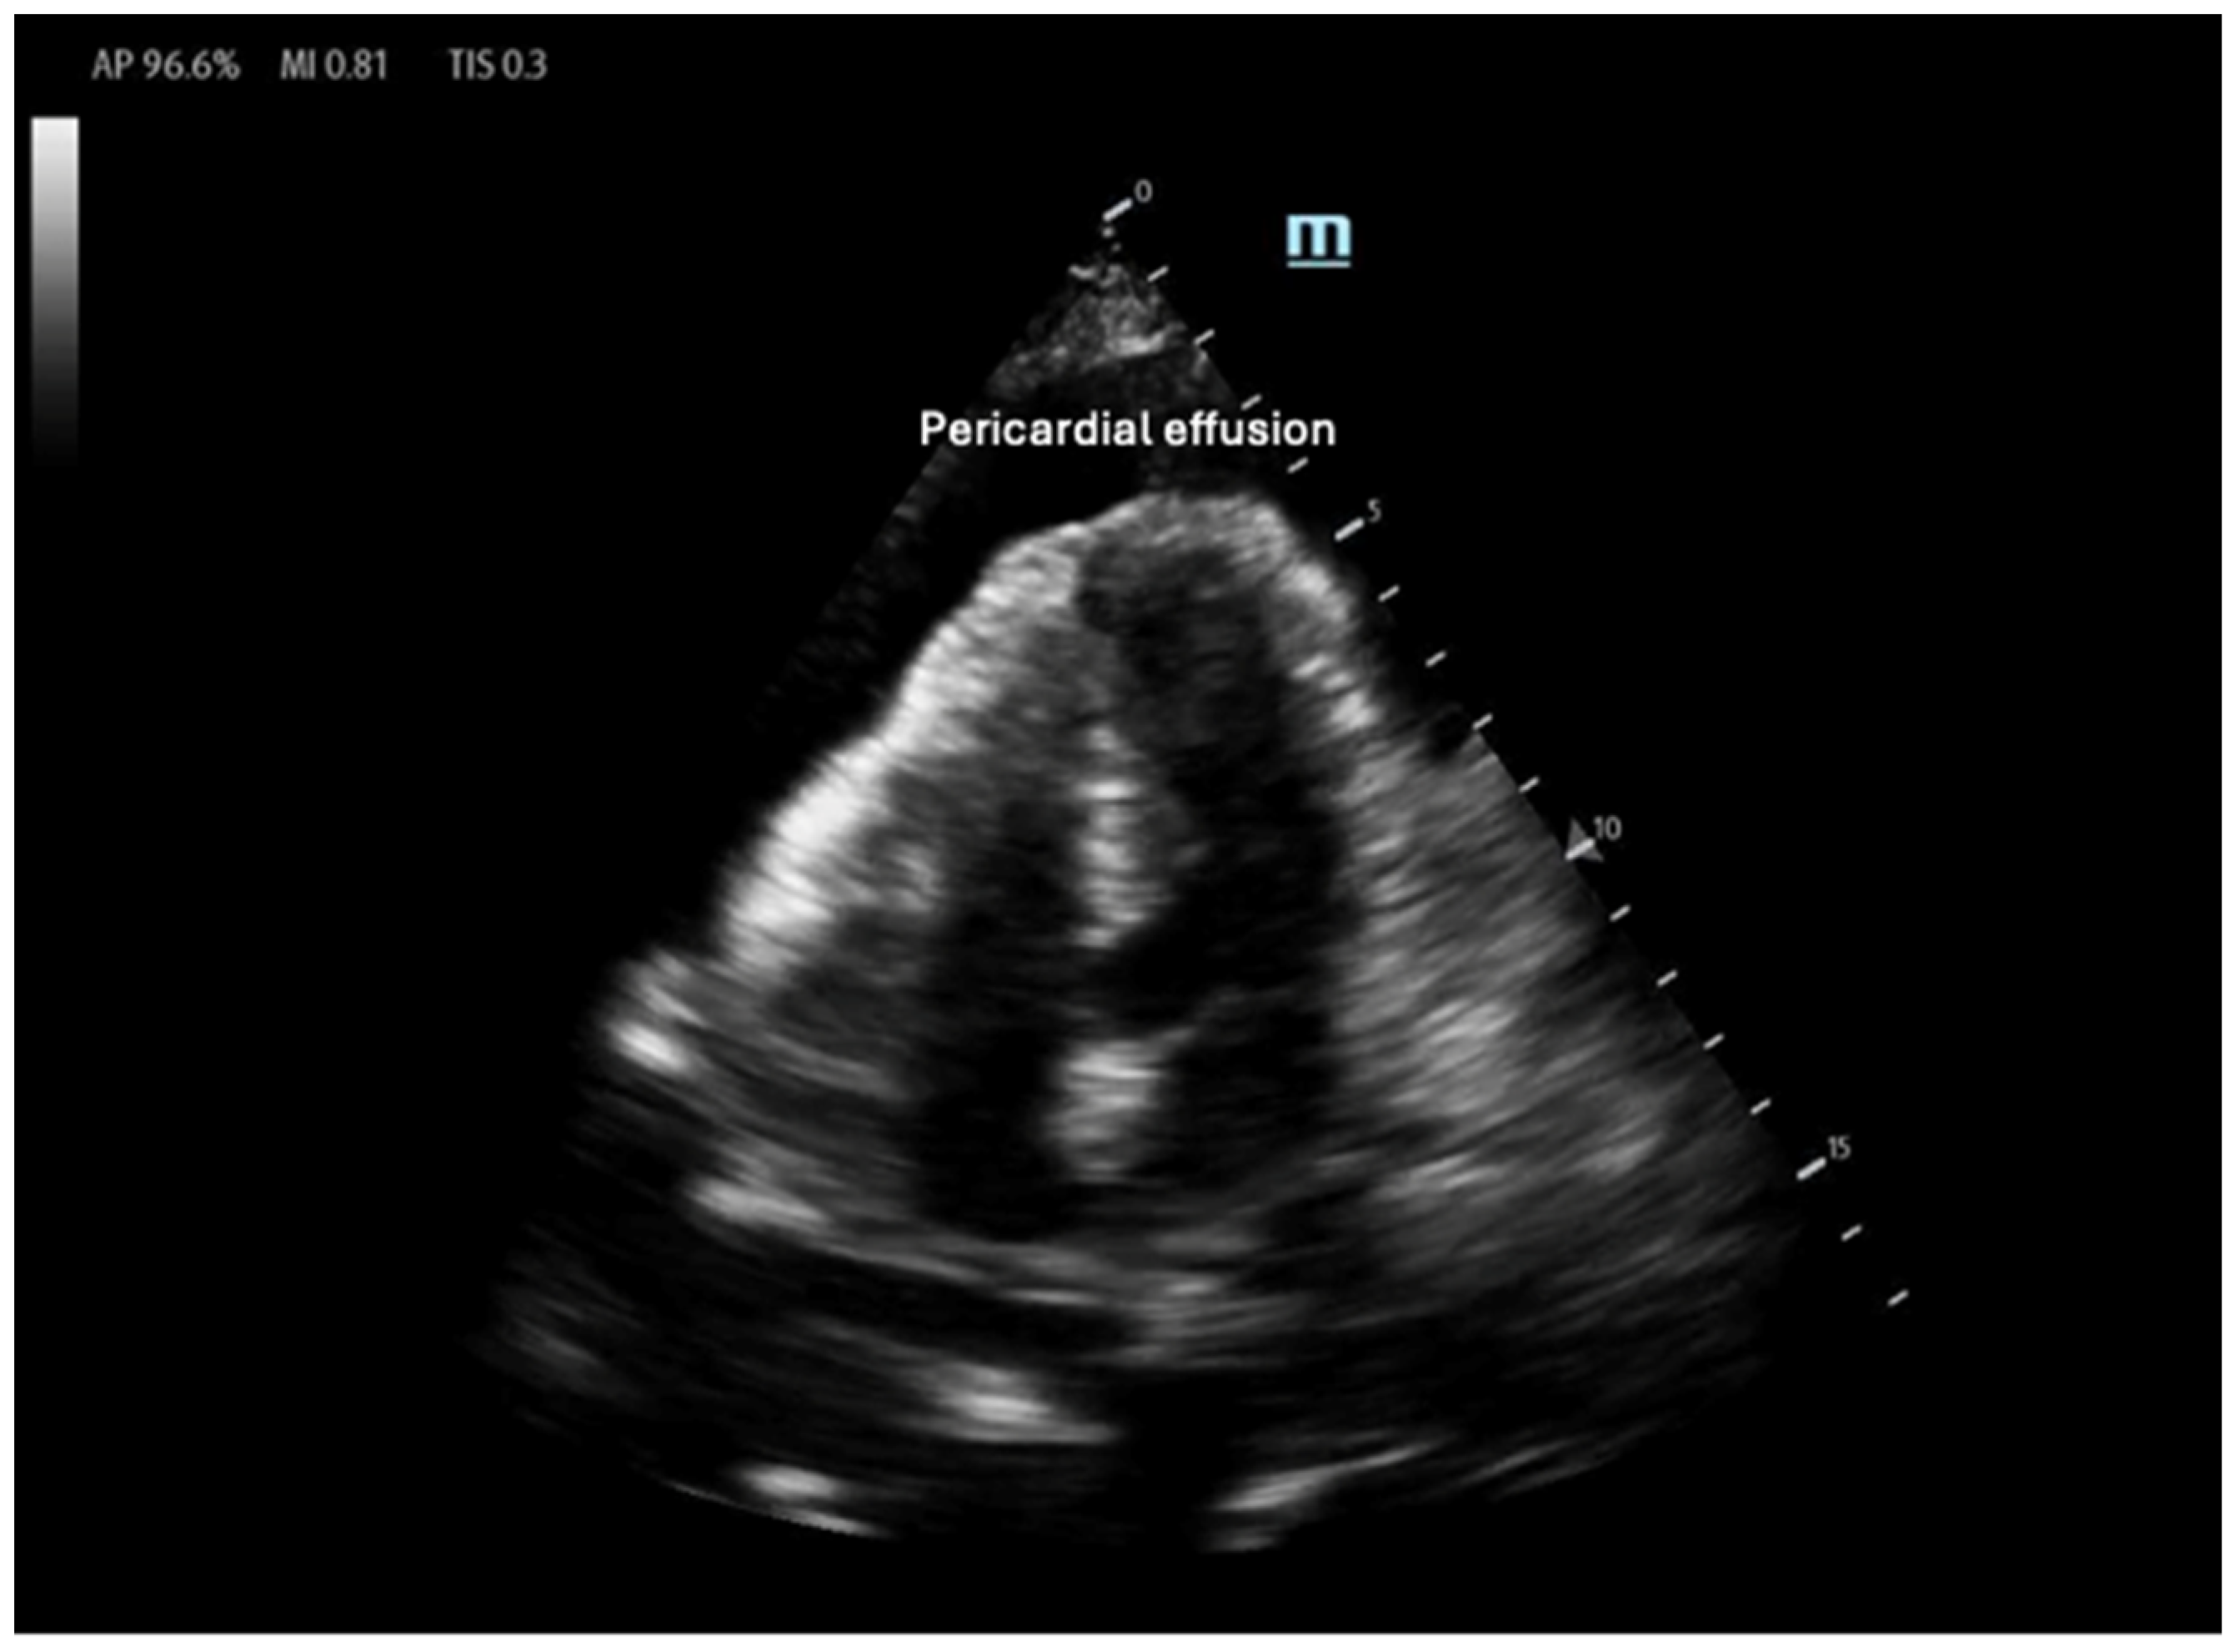

Right ventricular (RV) contractility is essential for maintaining right-sided cardiac output, ensuring blood supply to the pulmonary vasculature and subsequently to the left heart. Unlike the LV, the RV contracts primarily through longitudinal muscle fiber shortening, inward free wall movement, and LV-dependent contraction [32]. As a result, RV contraction occurs predominantly in a longitudinal rather than radial manner. Due to the RV’s greater compliance compared with the LV, its contractility and CO are highly influenced by changes in afterload, which will be discussed in the next section. External pressure changes, such as those seen in cardiac tamponade, can also significantly impact RV function. In tamponade, pericardial fluid compresses the heart chamber, elevating RV diastolic filling pressure and reducing RV output [33]. Owing to the RV’s increased compliance, the RA and the RV are the first chambers to collapse under increased pericardial pressure. Therefore, RA/RV collapse on bedside POCUS in the presence of a pericardial effusion should raise the suspicion of tamponade (Figure 5) [34].

Figure 5.

Anechoic pericardial effusion in apical 4-chamber view.